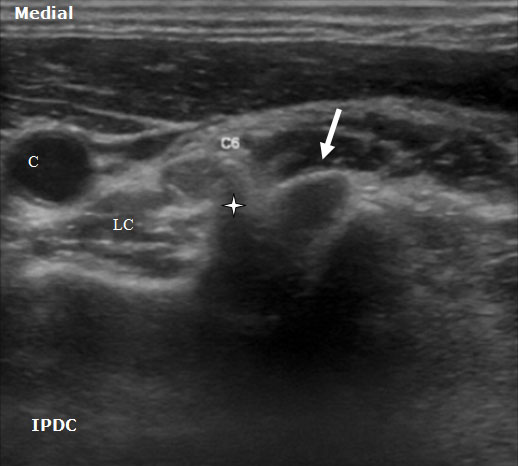

The sonoanatomy of the anterior and posterior tubercles associated with the transverse processes of the C4, C5, C6, and C7 vertebrae are used to identify their respective cervical nerve roots. The C7 vertebral body demonstrates an absent or rudimentary anterior tubercle with a prominent posterior tubercle (Figure 7). The anterior and posterior tubercles are seen as hyperechoic outlines with associated acoustic shadowing (hypoechoic area below). C6 has a sharp and prominent anterior tubercle and a shorter posterior tubercle. The nerve roots are viewed as homogeneous oval hypoechoic structures that exit through the transverse processes of the corresponding vertebral level. For example, the C6 nerve root will be seen between the anterior and posterior tubercles of the transverse process of C6 (Figures 8 & 9). The nerve roots differ in appearance from peripheral nerves below the clavicle which have a more hyperechoic appearance. As the transducer progresses to the more cephalad nerve roots, the anterior and posterior tubercles assume similar size characteristics (Figure 10) that have been referred to as the “2 humped camel sign.”[17] In approximately 90% of cases at the C7 level (Figure 7), the vertebral artery can be visualized prior to its entrance into the foramen at the C6 level.[10][18] Other important structures to visualize in the neck to assist with orientation include the thyroid, internal carotid artery, and jugular vein.

Figure 8. An axial ultrasound image at the C6 vertebral level demonstrating the nerve root (arrow) between the prominent anterior tubercle (star) and smaller posterior tubercle. LC= Longus Colli Muscle. C = Carotid Artery.

Figure 9. An axial ultrasound image at the C6 vertebral level demonstrating the nerve root and the prominent anterior tubercle (star). C = Carotid Artery.